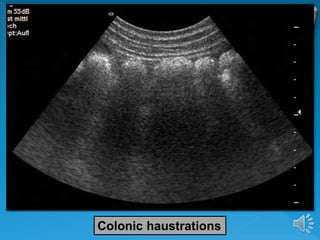

 The colon is characterized by its haustration

which using US is best visible at the ascending

and transverse colon.

 The left hemicolon is seen more often in a

contracted condition